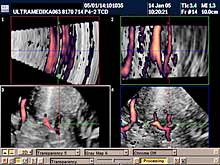

- transkranijalni kolor Doppler (TCD) i 3D CPA pregled

(otkrivanje

kritičnih stenoza, i proširenja-aneurizmi krvnih sudova mozga),

Primenjene tehnike:

- Broadband-CD,

- CPA,

- CPD,

- 3D CPD,

- Sono CT,

- XRes,

- 2D Broadband.